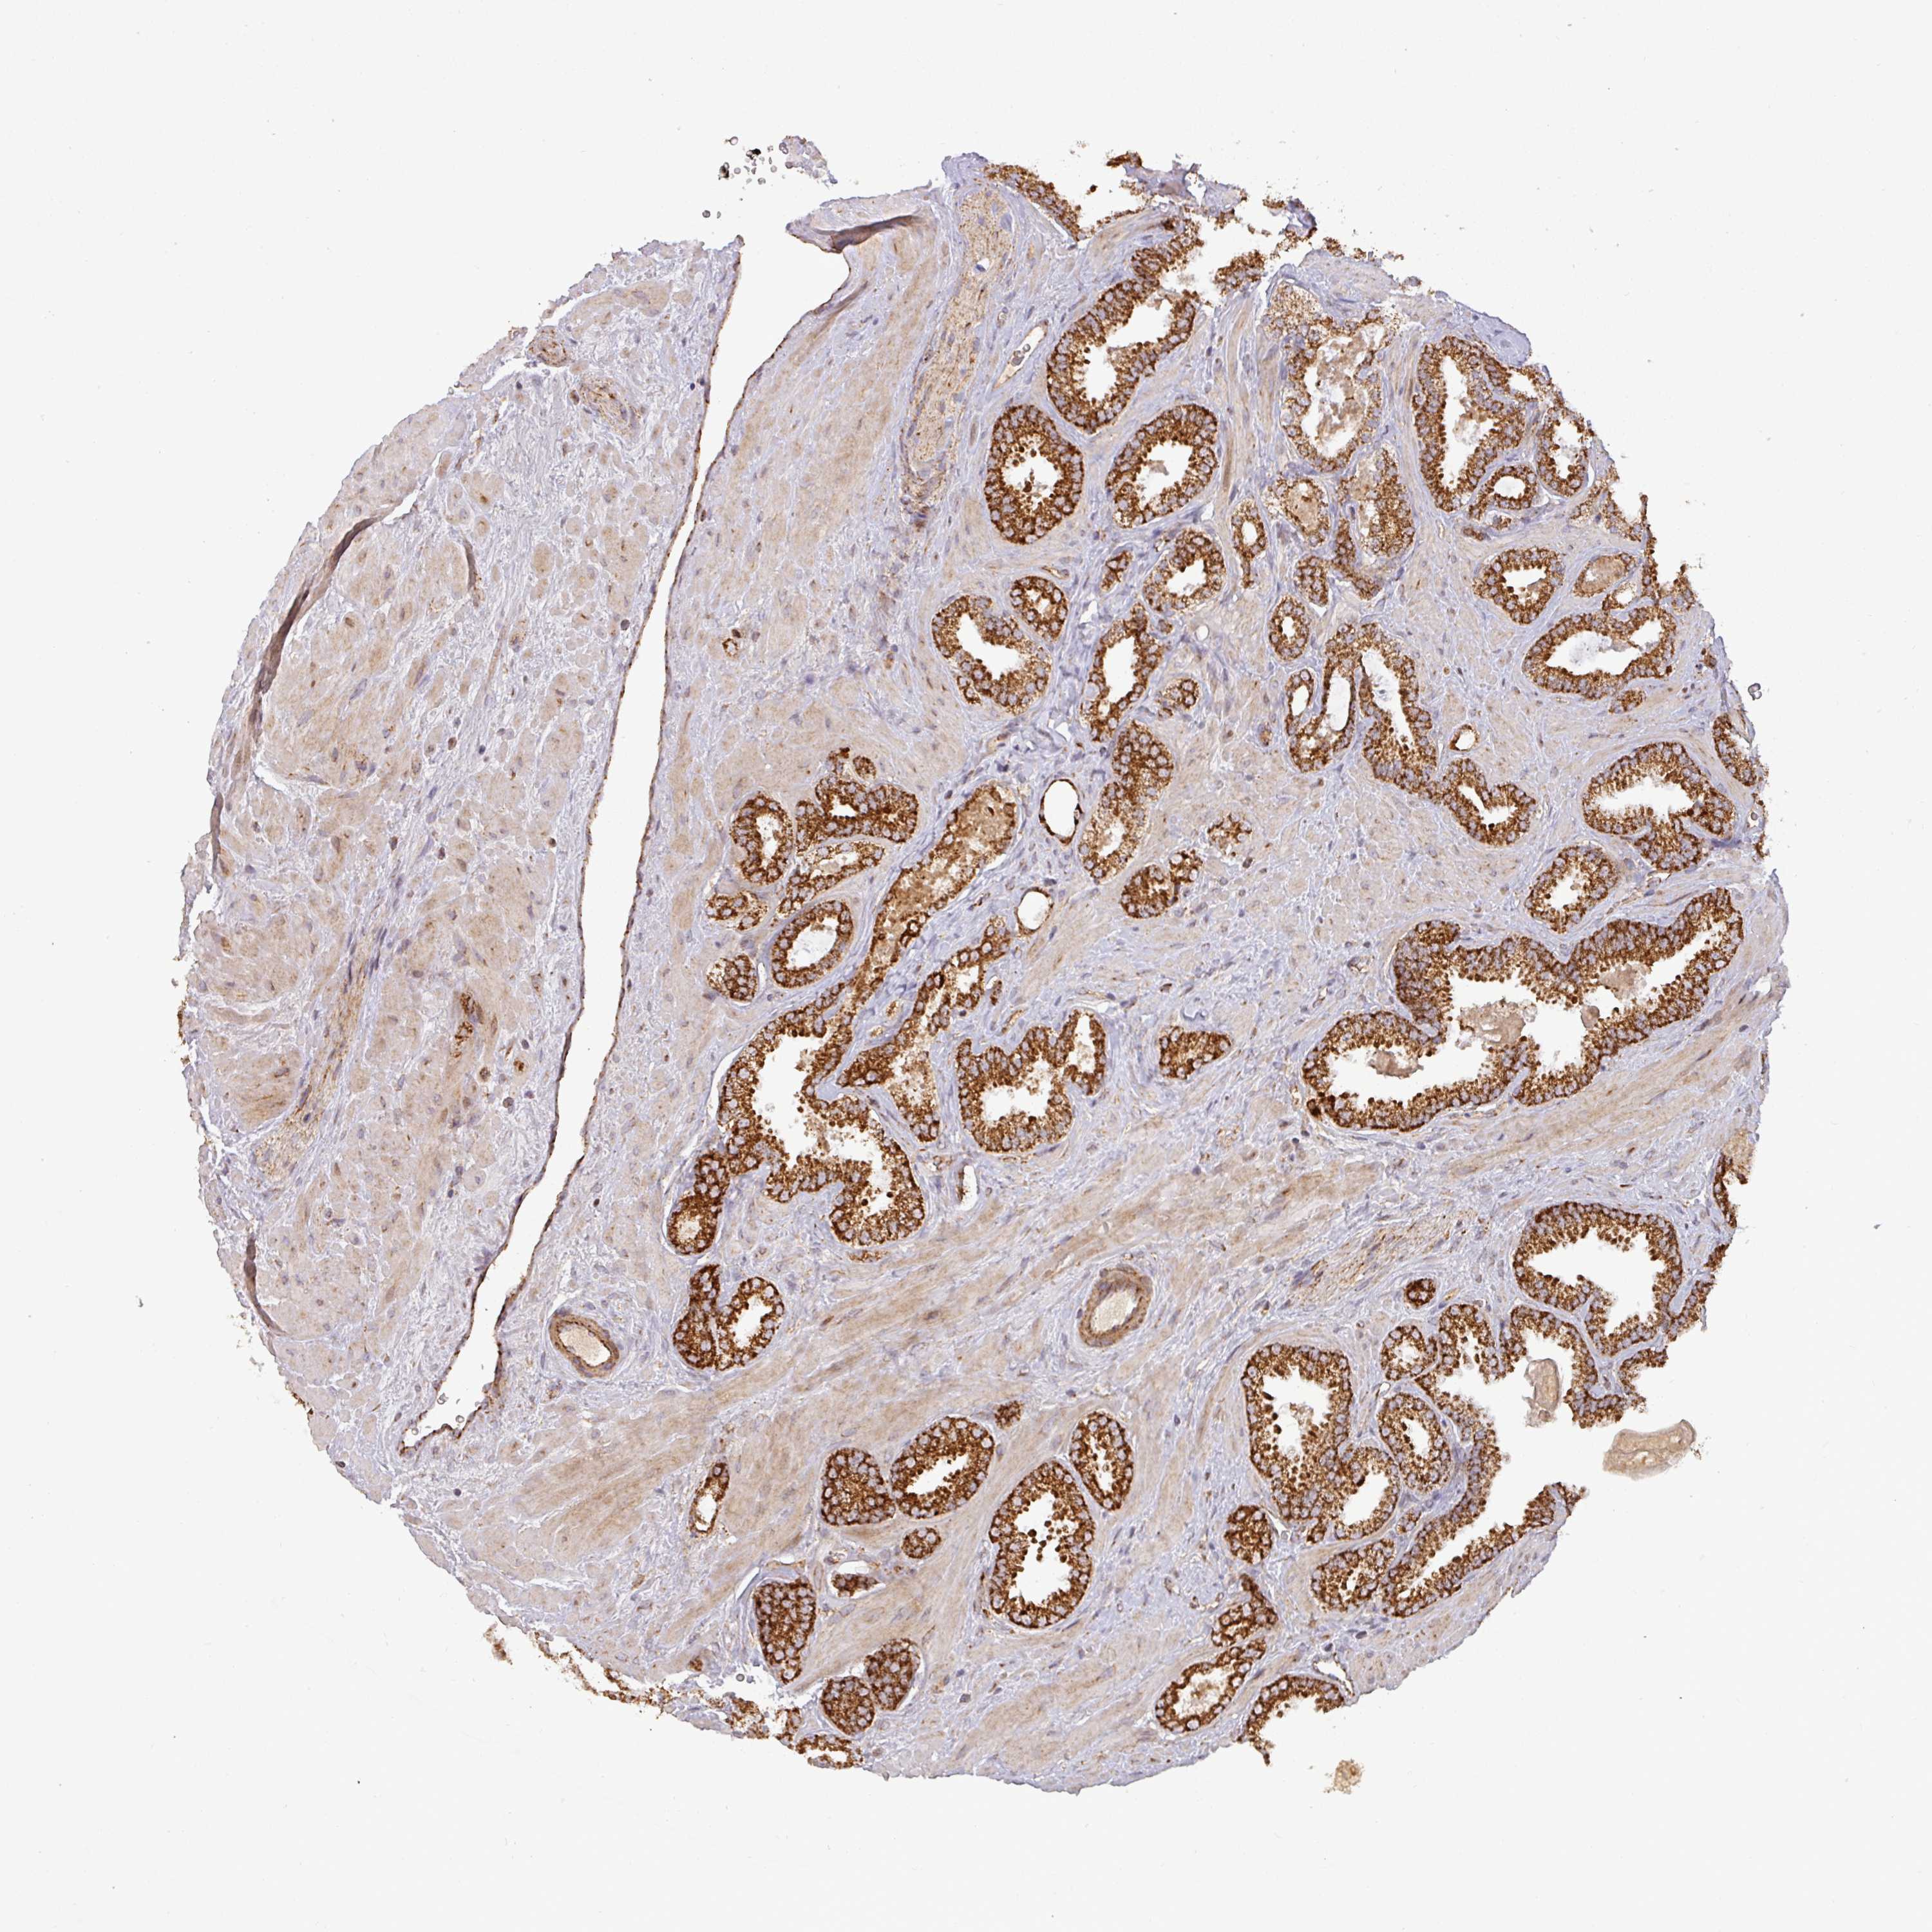

PROSTATE CANCER - Protein expressioni

A mouse-over function shows sample information and annotation data. Click on an image to view it in a full screen mode. Samples can be filtered based on level of antibody staining by selecting one or several of the following categories: high, medium, low and not detected. The assay and annotation is described here.

Note that samples used for immunohistochemistry by the Human Protein Atlas do not correspond to samples in the TCGA dataset.

Antibody stainingi

Antibody staining in the annotated cell types in the current human tissue is reported as not detected, low, medium, or high, based on conventional immunohistochemistry profiling in selected tissues. This score is based on the combination of the staining intensity and fraction of stained cells.

Each image is clickable and will lead to virtual microscopy that enables deeper exploration of all samples and also displays staining intensity scores, fraction scores and subcellular localization as well as patient and tissue information for each sample.

Antibody HPA008012

Antibody HPA045506

Staining

High

Medium

Low

Not detected

Intensity

Strong

Moderate

Weak

Negative

Quantity

>75%

75%-25%

<25%

None

Location

Nuclear

Cytoplasmic/membranous

Cytoplasmic/membranous,nuclear

Adenocarcinoma, Low grade

Adenocarcinoma, High grade